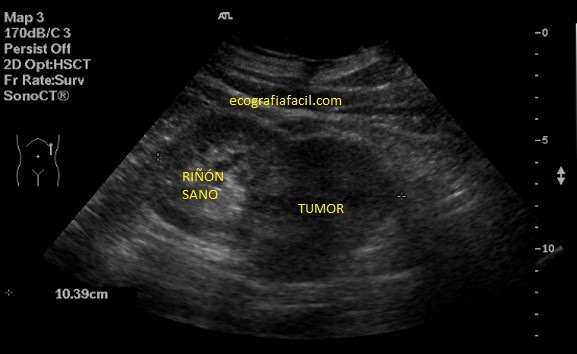

Tumores Renales:

En ecografía la mayoría de los tumores son sólidos.

Ecograficamente pueden ser hipoecogénicos, isoecogénicos, o hiperecogéncios y de gran variedad de formas.